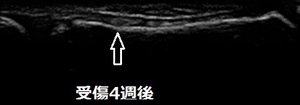

坂戸市 中学生。 右膝関節の痛み、オスグッドひざ。

体育祭の練習で100m走をしているとき、右膝に痛みを感じました。近隣の整骨院でランニング障害と

診断され、10日ほど電気治療とマッサージ、運動療法の施術を受けましたが、痛みは軽減せず、逆に痛みが

酷くなってしまいました。

当院の超音波検査では、右膝関節下の脛骨粗面軟骨が剥離していました(画像丸の中)。患部の外見上は

腫れているようには見えませんが、剥離している軟骨周囲は炎症で腫れているので、消炎に努めます。

また、同時に剥離した軟骨の癒合と膝関節周囲の筋緊張を緩和させる特殊な治療機器を使用して施術していき

ます。中学生は2週間でテニス部の練習に復帰し、ランニングをすることが可能となりました。来月の

公式戦に出場するために施術を継続中です。